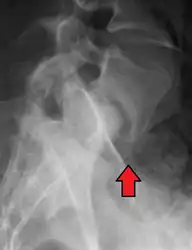

X-ray of measurement of spondylolisthesis at the lumbosacral joint, being 25% in this example. -